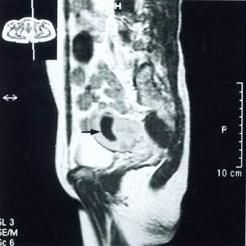

(三)B超、CT檢查及mri檢查

B超、CT檢查及mri檢查是臨床上最常採用的檢查方法,可確定腫塊的部位、大小、性質(如囊性或實性)與周圍組織的毗鄰關係等,但很少可以提示輸卵管來源。

輸卵管癌患者郭女士,54歲。婦檢:子宮前位,子宮正常大小,質中,無壓痛,宮頸光滑。左側附屬檔案可觸及約5.5cm×3cm大小包塊,右附屬檔案區未見異常。超聲檢查:子宮大小為4.8cm×3.5cm×4.1cm,包膜光滑,肌層回聲均勻,子宮內膜增厚,回聲稍增強,子宮左側見4.5cm×2.8cm的低回聲包塊,邊界清晰,形態為臘腸形欠規整,其內有回聲不均勻的低回聲改變。左側卵巢顯示不清。臨床診斷為:左側輸卵管癌治療:切除子宮及雙附屬檔案。術中見子宮正常大小,表面光滑。左側卵巢大小為2.0cm×1.8cm,左側輸卵管壺腹部明顯增粗、腫大,傘端封閉,形成大小為5.0cm×3.0cm臘腸樣腫塊,與周圍組織無明顯粘連,盆腔內未見腫大的淋巴結。右側附屬檔案未見異常。病理診斷結果:左側輸卵管低分化乳頭狀腺癌。經化療,情況良好。

患者,47歲,不規則陰道流血近1年,發現下腹部包塊6個月,近2個月陰道流黃水樣分泌物,時伴血性。曾抗炎治療10天,分泌物減少。自發病以來無腹痛。婦檢:宮體前位,正常大、質硬、活動性差、無壓痛、於子宮後方偏左可捫及鵝卵大腫物,活動性差,界限清、後方回聲增強。實驗室檢查:癌胚抗原正常,糖蛋白抗原-125異常增高。診斷為卵巢瘤,術見左輸卵管膨大10.0cm×5.0cm表面光滑,傘端呈菜花樣,與子宮直腸陷凹左側盆壁腹膜粘連。術中快速病理:左側輸卵管癌。行廣泛性子宮全切術,雙附屬檔案切除術及盆腔淋巴結清掃術。

⒈X線檢查:動態數位化子宮輸卵管碘油造影(HSG)有一定價值,但有可能引起癌細胞擴散至腹腔,一般不宜採用。近年採用CT確定腫塊的部位、大小、性質等。